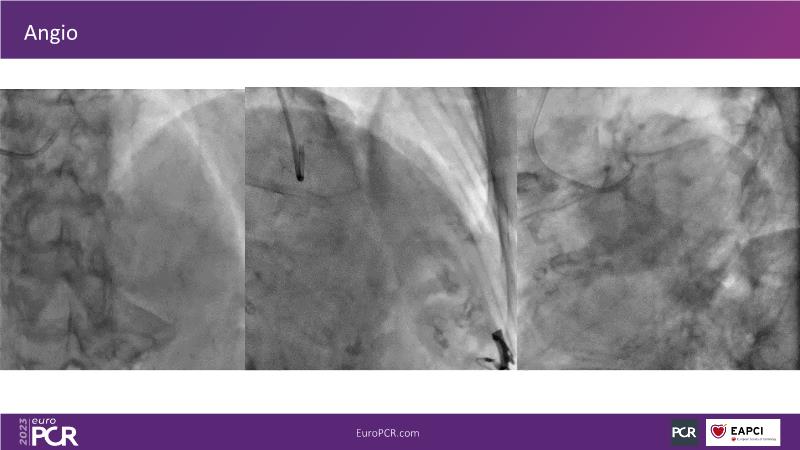

Join this session to explore the advantages of a fully optical approach in optimizing percutaneous coronary intervention (PCI) with the OptoWire III physiology wire and Nipro HF-OCT catheter. Through a practical case, you'll discover the significance of coronary physiology and intravascular imaging in bifurcation PCI and gain insights into how the performance and accuracy of the OptoWire III physiology wire can facilitate fast and reliable decision-making, particularly in side branch jailing scenarios.

- To discover the benefits of a fully optical approach to optimise PCI with OptoWire III physiology wire and Nipro HF-OCT catheter

- To review, through a practical case, the value of coronary physiology and intravascular imaging in bifurcation PCI

- To understand how the performance and accuracy of OptoWire III physiology wire can make the difference for fast and reliable decision-making in bifurcations, particularly through side branch jailing